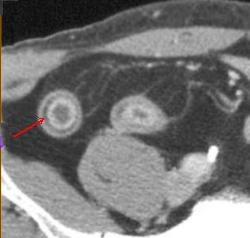

| Epaissisement parietale avec

oedeme de la sous muqueuse ( fleche rouge ) . Image

de fissuration legere peut se voyait un peut dans ce

cas . Maladie de Crohn de ileon en coupe TDM

coronale |